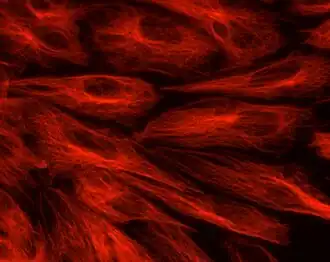

Una célula endotelial[1] es el tipo de célula plana que recubre el interior de todos los vasos sanguíneos (incluyendo los vasos capilares), y está en contacto permanente con la sangre. Poseen una longitud aproximada de 25 a 50 micrómetros (μm) y un ancho de 10 a 15 μm. Actúan como reguladoras del tráfico celular y molecular desde la sangre hacia el interior de los tejidos. Poseen una estructura altamente diferenciada y especializada con dos tipos de uniones entre células: unas estrechas (tigh) y otras débiles (gap). La célula endotelial sintetiza y libera sustancias vasoactivas que regulan el tono vascular, la presión sanguínea y el flujo sanguíneo local; también sustancias que participan en la coagulación, en la fibrinolisis y en reacciones inflamatorias e inmunológicas.[2][3]

Las células del endotelio presentan una longitud aproximada de 25-50 micrómetros (μm) y un ancho de 10-15 μm. Su eje mayor se dispone en paralelo a la dirección del flujo sanguíneo.[6][2]

Los bordes de las células endoteliales son irregulares, las células vecinas muestran interdigitaciones y tienen zonas serradas que se entrecruzan.

Cada célula endotelial tiene forma de placa curvada y delgada, de perfil poligonal, tiene un espesor central de 3-4 μm y de aproximadamente 0,1-0,4 μm en los bordes.[7]

El núcleo celular está muy aplanado y por eso aparece elíptico en los cortes histológicos. La región nuclear es la más gruesa de la célula y hace prominencia en la luz. La porción periférica y más delgada de la célula es tremendamente fina, y las membranas celulares que miran a la luz o al tejido están separadas por una capa de citoplasma de un grosor de 0,2-0,4 micras.

Se encuentra en la región cercana al núcleo, un complejo de Golgi y unas pocas mitocondrias, mientras que en la región delgada periférica del citoplasma hay elementos tubulares tortuosos del retículo endoplásmico. Son raros los lisosomas, pero no son infrecuentes los cuerpos multivesiculares.[8]